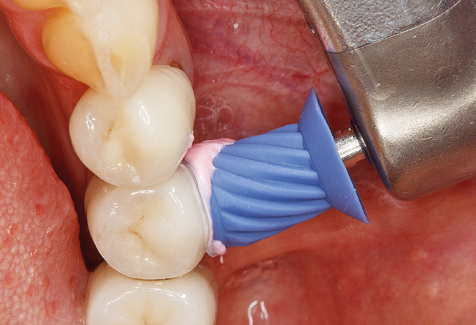

Dopo la pulizia meccanica delle superfici dei denti e degli impianti, le superfici dei denti naturali vengono pulite manualmente utilizzando strumenti manuali standard. Quando si esegue la pulizia manuale, è necessario prestare particolare attenzione a mantenere il corretto angolo di applicazione, un'adeguata nitidezza, un buon supporto e lavorare con la curette dall'apicale al coronale. Curette in titanio o carbonio devono essere utilizzate per la post-pulizia delle strutture dell'impianto (Fig. 8). Oltre all'uso di dispositivi ad ultrasuoni, i dispositivi power jet possono essere utilizzati anche in odontoiatria conservativa. Tuttavia, si deve considerare che queste procedure non sono adatte per rimuovere depositi duri e quindi non possono sostituire completamente l'uso di strumenti manuali e strumenti ad ultrasuoni. In tutti i casi, la pulizia è seguita dalla lucidatura meccanica del dente accessibile e delle superfici dell'impianto con ventose e composti di lucidatura (Fig. 9).